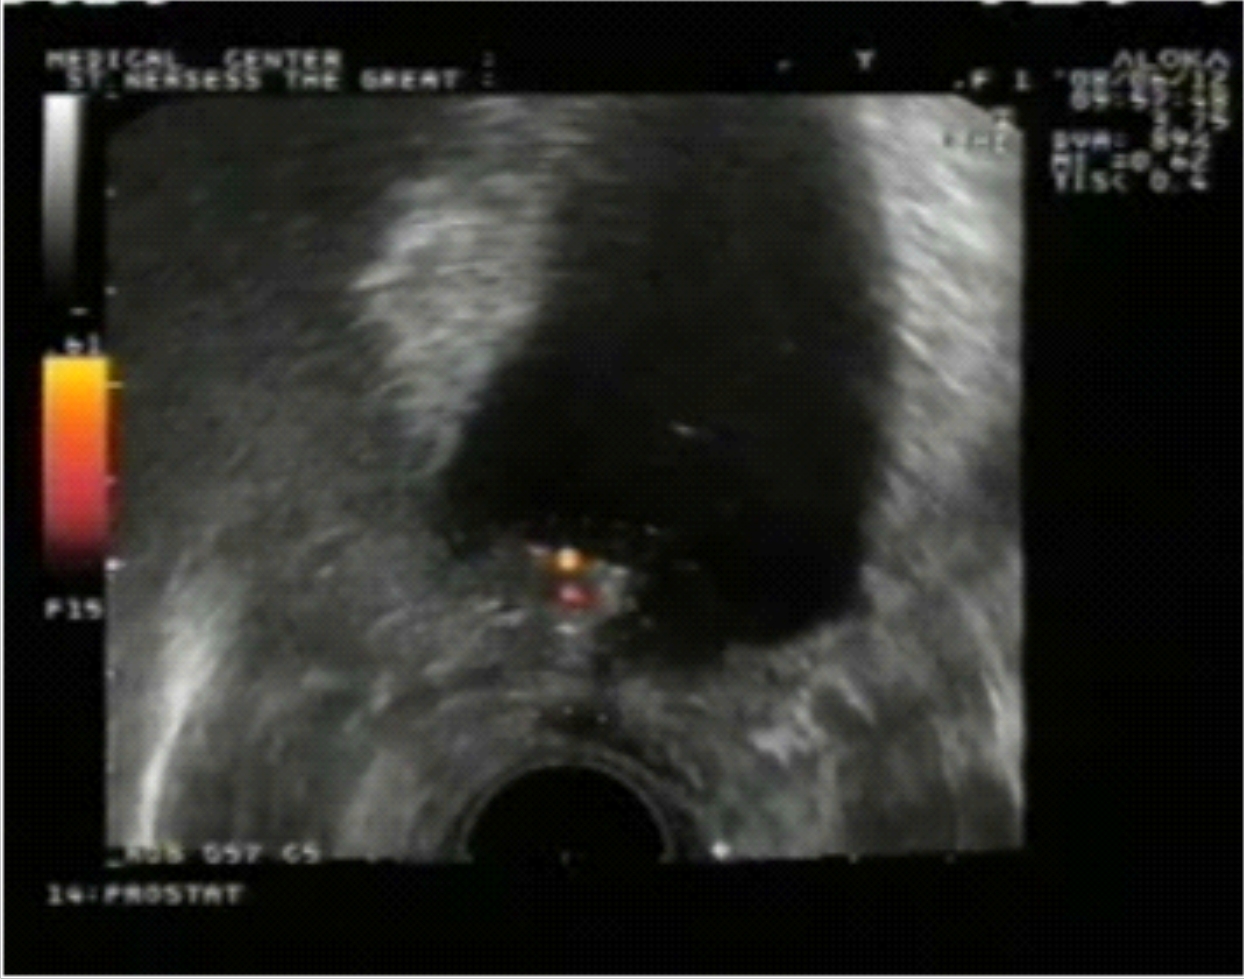

Վերջում ցանկանում ենք ներկայացնել մեր հետազոտությունների ժամանակ տրանսռեկտալ ուլտրաձայնային հետազոտության միջոցով հայտնաբերված տեղային ռեցիդիվի դեպք, որը դիտվել է գորշ սանդղակ (նկ. 1) և էներգետիկ դոպպլեր ռեժիմներով (նկ. 2): Սկանավորումը կատարվել է արմատական պրոստատէկտոմիայից 6 ամիս անց: Միզապարկի վզիկի աջ հատվածում` բերանակցման զոնային հարակից երևում է հիպերվասկուլյար օջախ, որը տրանսռեկտալ թիրախային բիոպսիայով ախտորոշվել է շագանակագեղձի ադենոկարցինոմա (Գլիսոն 3+4=7 բալ):

Նկ. 1 Նկ. 2